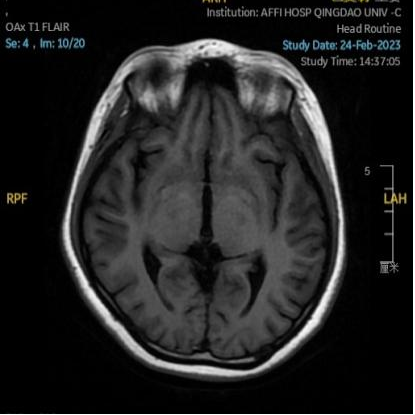

2023.03.27颅脑MR平扫示双侧基底节区及桥脑异常信号,考虑渗透性脱髓鞘综合征,较前范围略减小,请结合临床,见图4。

图4 2023.03.27双侧基底节区及桥脑见对称性片样长T1长T2信号,FLAIR呈高信号,较2023-02-24MR所示范围减小。脑室、脑池、脑沟、脑裂未见明显异常,中线结构居中。